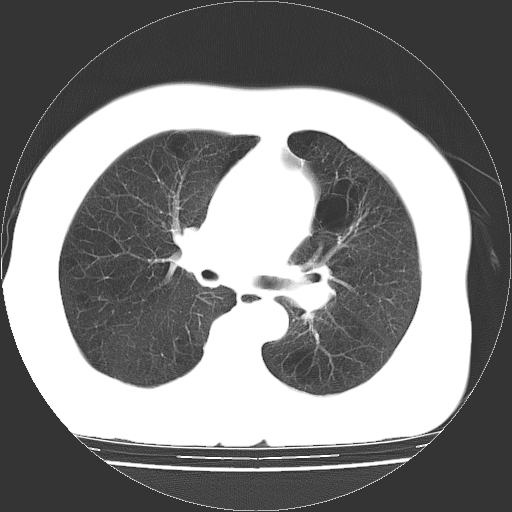

标题: CT13141:女,70岁,咳嗽、胸闷半个月。 [打印本页]

标题: CT13141:女,70岁,咳嗽、胸闷半个月。

女,70岁,咳嗽、胸闷半个月。纵隔窗未见异常,未上传。

小叶中心型肺气肿并多个肺大泡形成

慢性支气管炎合并小叶中心性肺气肿,多发性肺大泡

慢性支气管炎并小叶中心性肺气肿及间隔旁肺气肿.(多与吸烟有关)。